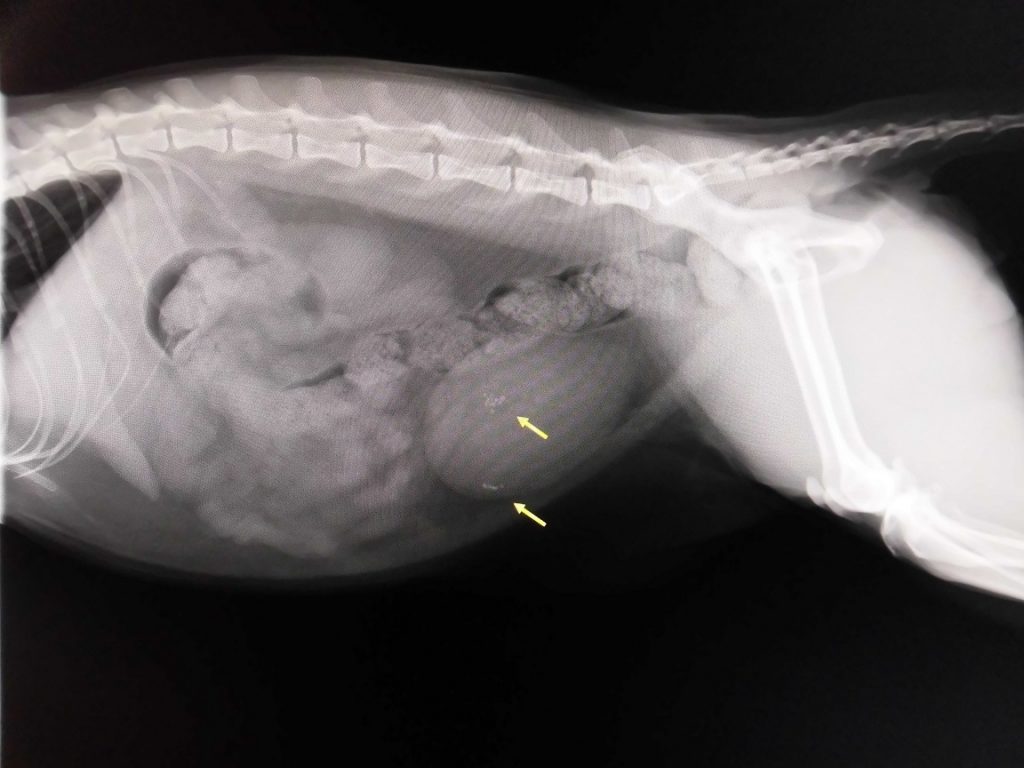

こちらがレントゲン画像ですが、膀胱内に多くの小さな結石が確認できます。

超音波検査やレントゲン検査では膀胱内に数㎜の結石が多数確認されており、内科治療での改善はみられないとのことで外科手術を実施することになりました。